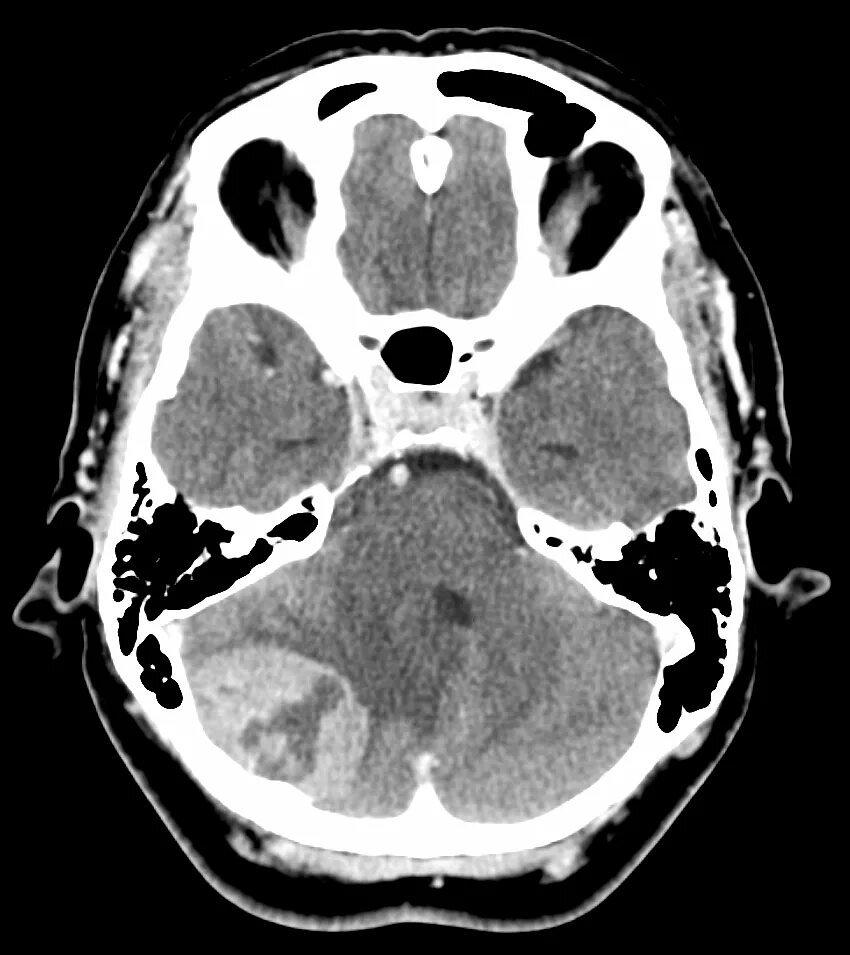

Болит кт